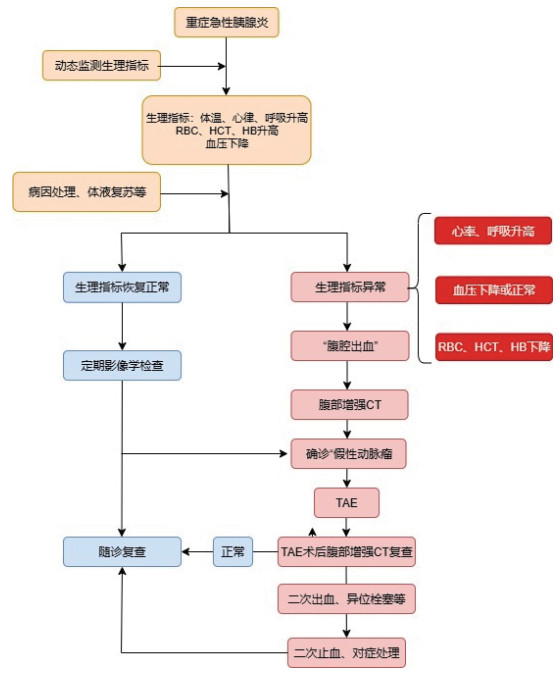

重症急性胰腺炎的早期,由于炎症反应,血管内皮损伤和血管通透性增加,液体转移到腹膜和间质,同时还因呕吐、经口摄入减少、经呼吸道蒸发增加和出汗等导致血管内血容量减少[3-4](仅有血浆的减少,无血细胞的丢失),血液浓缩,RBC、HB、红细胞比容(HCT)升高,体温上升、心率升高、血压下降、呼吸加快等;针对患者早期症状进行病因处理、积极适当体液复苏等;患者通过液体复苏,血容量增加,低血容量症状改善,HB、RBC、红细胞比容(HCT)下降恢复至正常水平,体温、心率、血压、呼吸恢复正常;但患者在治疗过程中由于各种原因出现“腹腔出血”时,大量血液从血管内丢失,血容量减少(全血丢失),尽管通过静脉补液,血容量恢复,血压正常,低血容量症状改善,但由于血细胞及血红蛋白的合成需要一定时间,故患者的RBC、HB、红细胞比容(HCT)降低,致使患者的血液载氧能力下降,从而可能出现一系列的贫血症状(头晕、头痛、呼吸短促、脸色苍白等),患者临床症状未能改善,2024美国胃肠道病学会[5]建议尽快进行CT检查探寻原因;若在患者恢复过程中出现“腹腔出血”,患者血容量大量丢失(全血丢失),血压下降、心率代偿性升高,RBC、HB、HCT(血细胞比容)降低,出现低血容量休克。在重症急性胰腺炎治疗、恢复过程中前后生理指标对比见图 4。

| 图 4 重症急性胰腺炎治疗恢复中有无 |

在现有的专家指南及研究报告中[2, 5-7],对于急性胰腺炎的治疗过程中出现“腹腔出血”并发症,仅对其治疗进行阐述,未对其过程进行系统的说明,本研究旨在强调在急性胰腺炎治疗过程中密切关注患者的临床表现、动态监测患者的生理指标等、加强临床医务人员对“腹腔出血”并发症的认识,尽早的发现诊断“腹腔出血”并发症并进行处理。

总之,重症急性胰腺炎导致的胰周动脉破裂出血及假性动脉瘤形成采取介入治疗效果满意、长期随访并发症发生率低,但需术者熟练掌握技术要点并注意操作手法。在患者诊断为重症急性胰腺炎后,应积极进行治疗,阻碍患者病情进一步发展,降低并发症的发生率,同时在重症急性胰腺炎的治疗恢复期间,应密切关注患者的临床表现、生理指标等,对于经治疗后症状无改善患者进行CT检查查明原因,正常患者定期进行影像学检查排除假性动脉瘤等并发症的形成发展,一旦发现假性动脉瘤形成,应在常规治疗的情况下立即进行TAE,降低患者的并发症发生率及病死率,同时术后应积极进行影像学复查,排除介入手术术后并发症,具体诊治过程参考图 4。